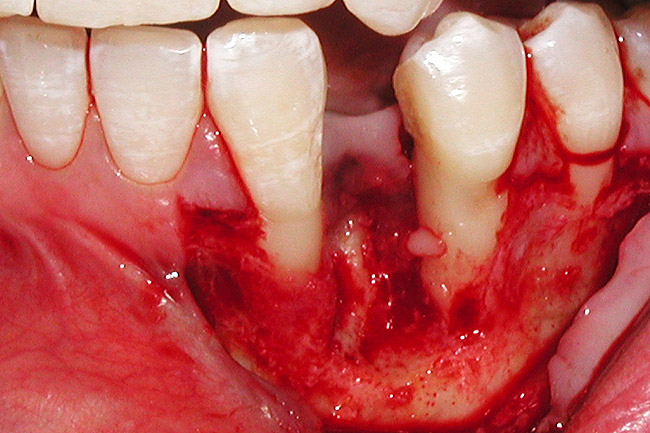

The patient had no medical concerns and had a history of an implant placement in December 2002 when she was 25 years old. In February 2005, she presented with a mobile implant and an associated advanced peri-implantitis. Radiographic review at the initial examination demonstrated significant destruction of the dentoalveolar ridge around the implant as well as around the adjacent natural dentition. Emergency-based treatment involved surgical implant removal only and debridement of the infection (Figure 4 and Figure 5). Following uneventful healing, an advanced ridge defect was apparent at the edentulous site and moderate and advanced attachment loss noted at No. 22D and No. 21M, respectively (Figure 6 and Figure 7). This case demonstrates bone loss of two separate origins: lack of bone because of tooth agenesis and destruction of bone from inflammatory peri-implantitis.

Figure 4  Vertical ridge defect in site No. 22.

Figure 4

Figure 5  Horizontal ridge defect in site No. 22.

Figure 5